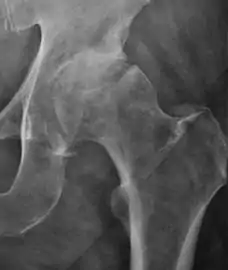

Radiological signs of transient osteoporosis of the hip include localized osteoporosis of the femoral head and neck (Figure 8). Nevertheless, final diagnosis has to be made with MRI to differentiate it from avascular necrosis and from insufficiency or stress fractures of the femoral head or neck. In case of AVN, radiographs can only demonstrate delayed or advanced signs. Staging according to Ficat classification ranges between normal appearance (stage I), slight increased density in the femoral head (stage II), subchondral collapse of the femoral head with or without “crescent” sign (stage III), and advanced collapse with secondary osteoarthritis (stage IV). In the case of stress or insufficiency fractures X-ray sensitivity has been proven to be much lower than MRI, which is currently the gold standard.[1]

Figure 8:

X-ray of a patient with transient osteoporosis of the left hip showing osteoporosis.[1]

Coronal stir imaging in transient osteoporosis, showing diffuse edema.[1]

Scintigraphy (A), sagittal T1 (B), and coronal PD fat sat of a patient with a subchondral fracture of the femoral head with convex shape to the articular surface.[1]

Coronal T1 of a patient with avascular necrosis of the femoral head.[1]